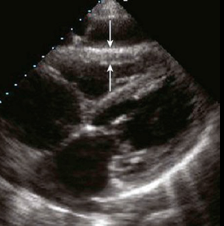

- Flattening of the interventricular septum with a “D” Sign on the parasternal short axis (4; 5; 8)

“D” sign – septal bowing